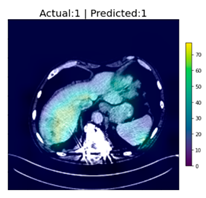

| 1 | ![]() | Has Tumor | Has Tumor | Has Tumor | Some |

| 2 | ![]() | Has Tumor | Has Tumor | Has Tumor | Yes |

| 3 | ![]() | Has Tumor | Has Tumor | Has Tumor | Yes |

| 4 | ![]() | Has Tumor | Has Tumor | Has Tumor | Yes |

| 5 | ![]() | Has Tumor | Has Tumor | Has Tumor | Yes |

| 6 | ![]() | No Tumor | Has Tumor | Has Tumor | Yes |

| 7 | ![]() | Has Tumor | Has Tumor | Has Tumor | Yes |

| 8 | ![]() | Has Tumor | Has Tumor | Has Tumor | Yes |

| 9 | ![]() | Has Tumor | Has Tumor | Has Tumor | Some |

| 10 | ![]() | Has Tumor | Has Tumor | Has Tumor | Yes |

| 11 | ![]() | Has Tumor | Has Tumor | No Tumor (Cyst) | Some |

| 12 | ![]() | Has Tumor | Has Tumor | Has Tumor | Yes |

| 13 | ![]() | Has Tumor | Has Tumor | No Tumor | Yes |

| 14 | ![]() | Has Tumor | Has Tumor | No Tumor (Inflammation of the Biliary Tract) | Some |

| 15 | ![]() | No Tumor | Has Tumor | No Tumor (Cyst) | Some |

| 16 | ![]() | Has Tumor | Has Tumor | Has Tumor | Yes |